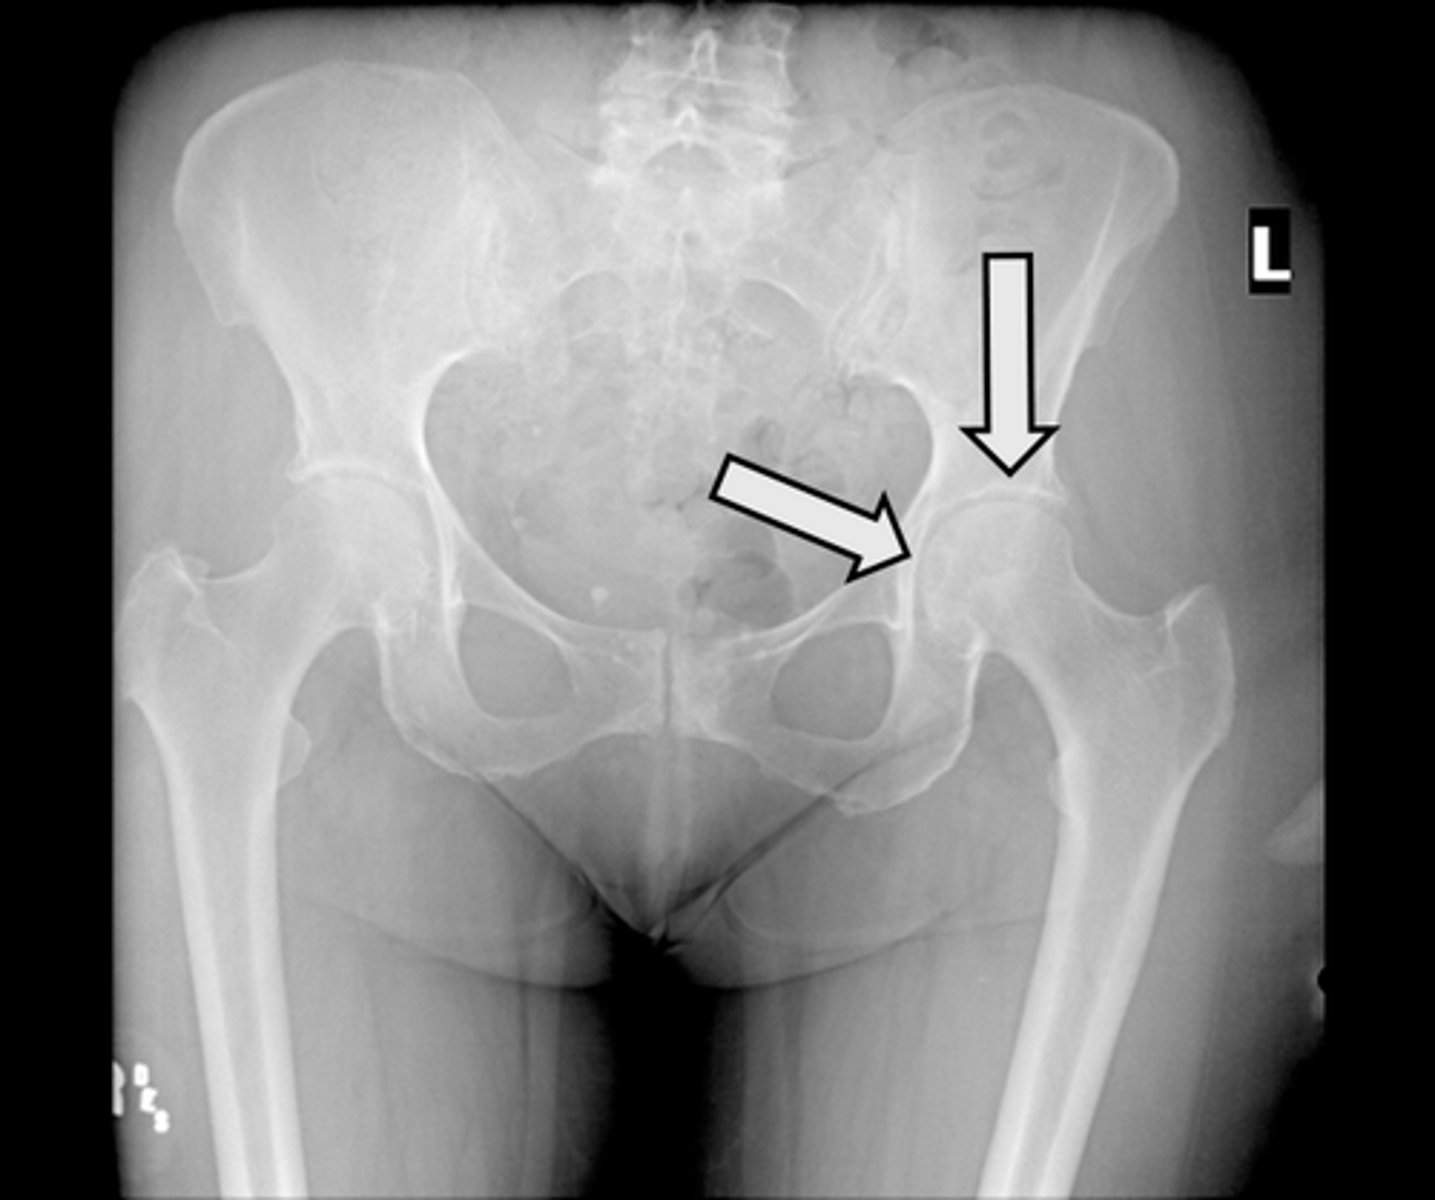

AP pelvis

What is the image?

<p>What is the image?</p>

L acetabulum

What is indicated in the image?

L anterior superior iliac spine (ASIS)

L ilium

L ischial tuberosity

L obturator foramen

L sacroiliac joint

L superior ramus of pubis

R acetabulum

R anterior superior iliac spine (ASIS)

R ilium

R ischial tuberosity

R obturator foramen

R sacroiliac joint

R superior ramus of pubis

Sacrum